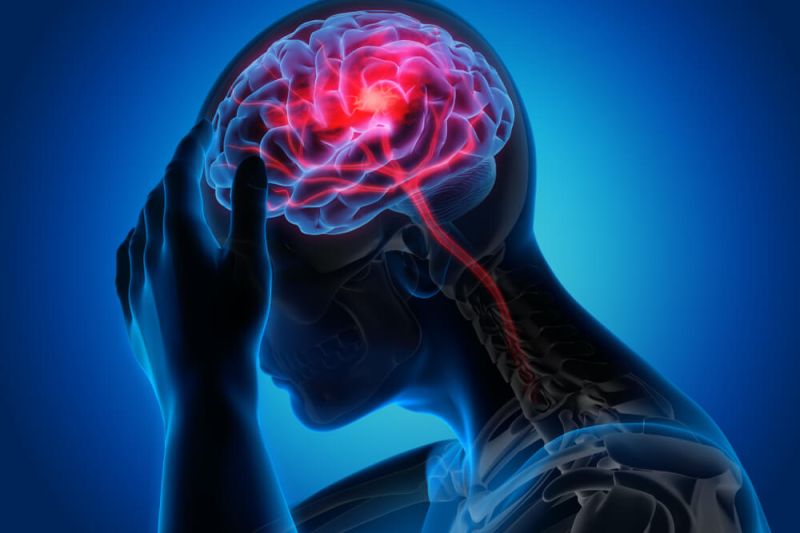

Com dois anos de existência, a AbraRio fornece produtos com Cannabis para mais de mil pessoas que convivem com diversas condições de saúde. A interrupção do tratamento pode prejudicar consideravelmente o bem-estar desses pacientes.

Se você optar por um tratamento com Cannabis, é fundamental começar pela recomendação de um médico. Aqui na plataforma de agendamentos do Cannabis & Saúde, você pode marcar uma consulta com algum dos nossos médicos prescritores.